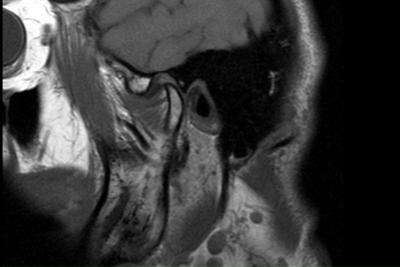

Во время исследования послойно, с минимальным "шагом" (расстоянием) сканируются ткани, создавая изображения ("срезы"), которые позволяют выявить даже минимальные изменения в костях, мягких тканях, хрящах и сосудах. МРТ - это самый информативный метод исследования, в ходе которого диагностируются новообразования, очаги воспаления, травматические повреждения и т.д.

МРТ ВНЧС позволяет оценить всю анатомическую зону, включая граничащие с суставом структуры.